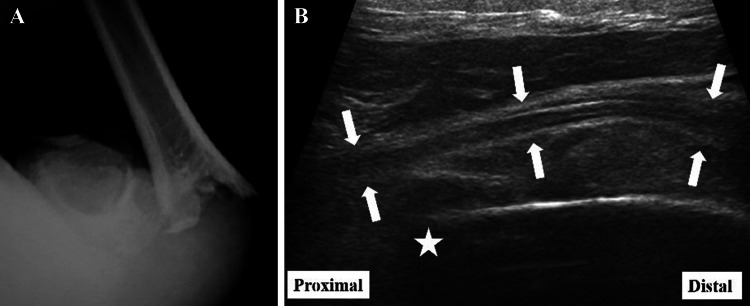

Fig. 1.

Case 9: 10-year-old boy with supracondylar humerus fracture without the complete radial nerve palsy. a Anteroposterior X-ray showed a Gartland type III supracondylar humerus fracture. b The longitudinal sonography of the radial nerve (white arrows) showed the nerve had a normal fibrillar pattern and no contact with the fragment at the fracture site (white star)